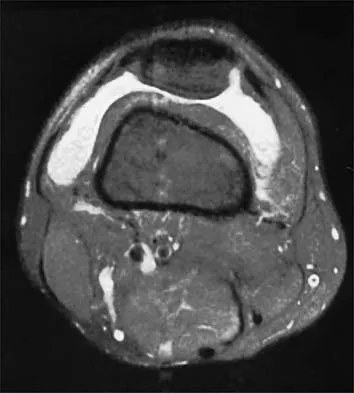

A 30-year-old man who participates in recreational sports reports the spontaneous onset of intermittent pain and swelling about the right knee. Examination reveals a 3+ effusion, with a range of motion of 10 degrees to 60 degrees. He has mild diffuse tenderness but no instability. MRI scans and an arthroscopic view are shown in Figures 39a through 39c. Management should consist of

Explanation